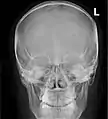

![]() Paranasal sinuses seen in a frontal view | |

Paranasal sinuses radiograph (occipitofrontal)

Paranasal sinuses radiograph (occipitomental)